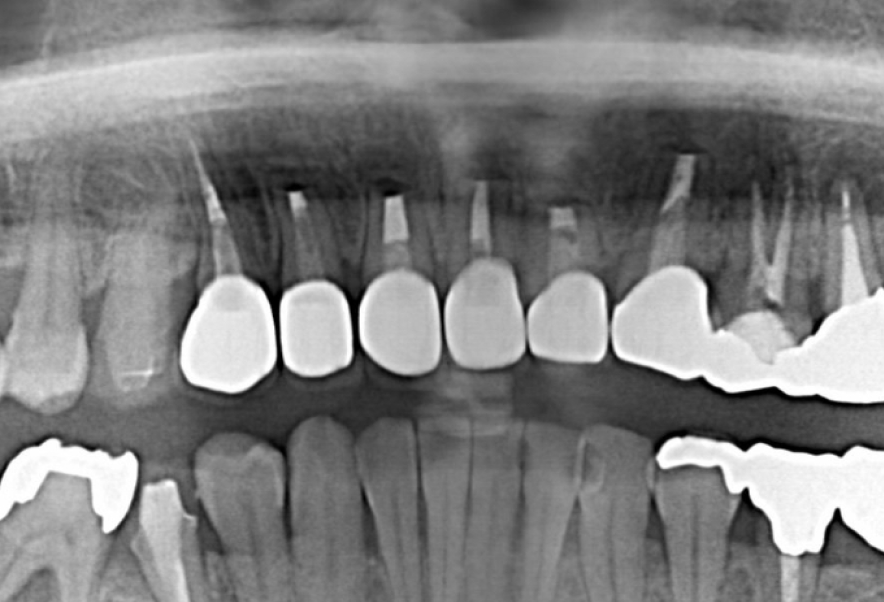

Before

After

他院で保険外根管治療・歯根端切除手術をしセラミックを装着後

すぐ膿んできた歯の再治療